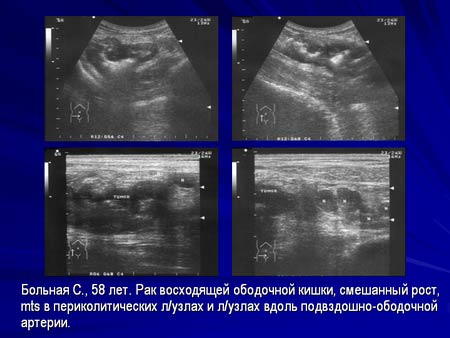

Ультразвуковая диагностика опухолевых заболеваний ободочной и прямой кишок.

Часть 1: Ультразвуковая семиотика.